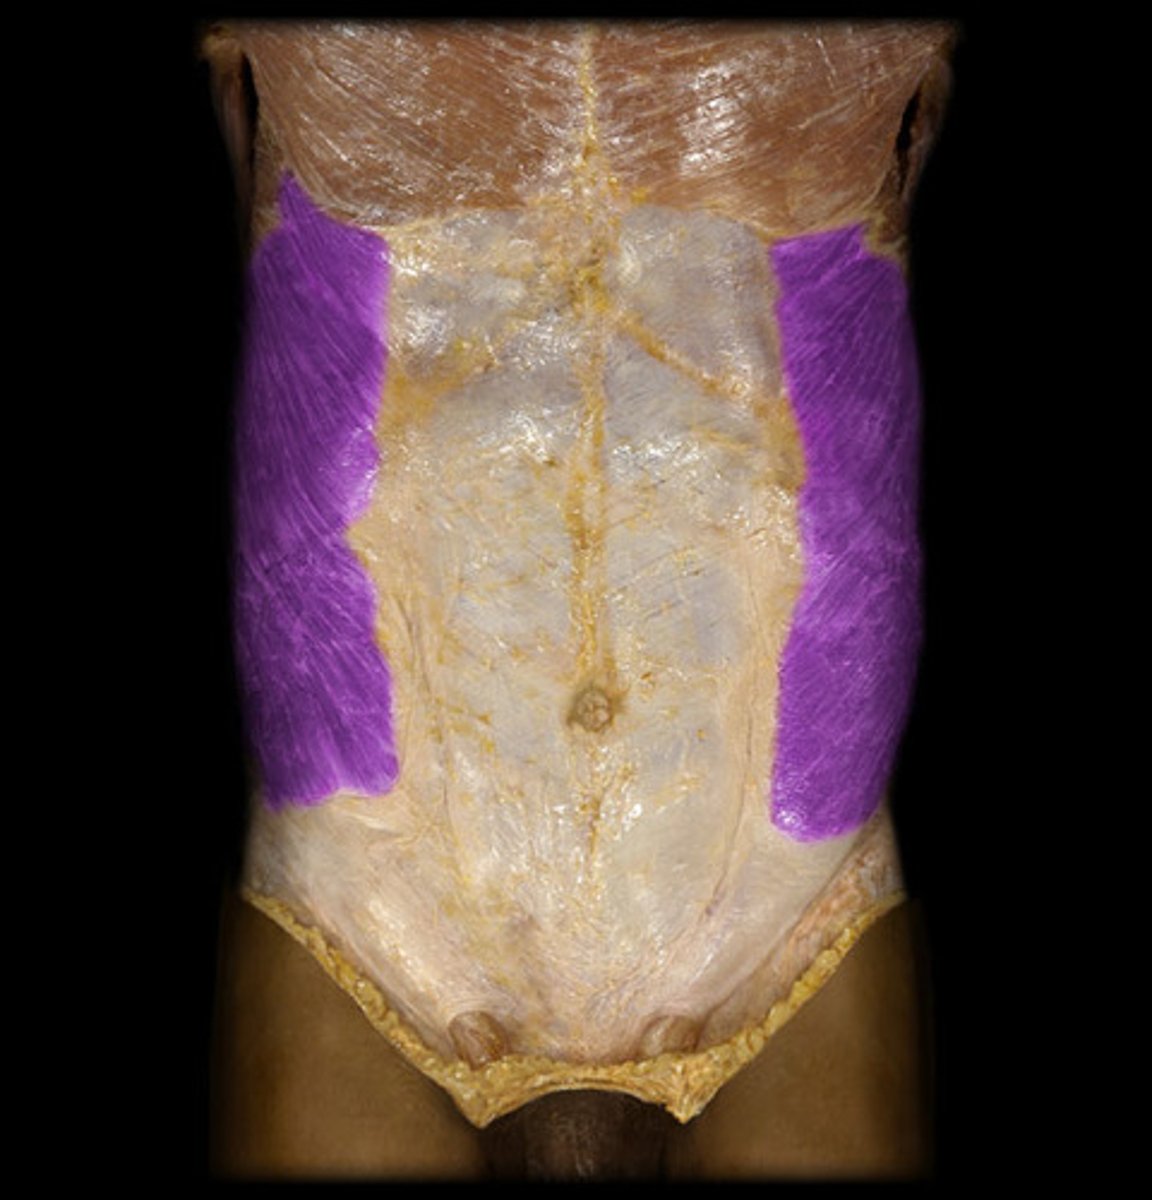

external oblique

internal oblique